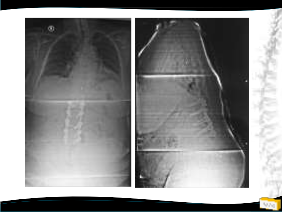

OLGU

• 54y, K

• Bel ve her iki bacak ağrısı

• NM normal

2011

2009 2011